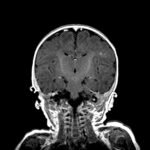

Infant tuberculosis (TB) is a rare but potentially deadly infection and difficult to diagnose, especially in infants who may present with non-specific symptoms. Here, we report a case of an United States-born term infant with community-acquired miliary TB and no confirmed TB exposure history. The patient initially presented with respiratory distress at seven weeks of life with chest radiograph showing a right lower lobe (RLL) infiltrate. After failing multiple courses of treatment for community-acquired pneumonia and developing growth faltering, the patient had imaging findings suggestive of TB infection with CNS involvement. The diagnosis of TB was confirmed by QuantiFERON and purified protein derivative (PPD). In infants who fail conventional treatment for bacterial pneumonia, the differential should be broadened to consider alternative etiologies. Additionally, brain imaging should be performed in cases of disseminated TB despite negative cerebrospinal fluid (CSF) studies since these patients are at high risk of central nervous system (CNS) involvement.